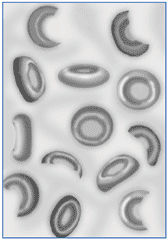

Гемолитическая анемия (лат. anaemia haemolytica от др.-греч. αἷμα «кровь» + λύσις «разрушение, растворение» + анемия) — групповое название редких заболеваний, общим признаком которых является усиленное разрушение эритроцитов, обусловливающее, с одной стороны, анемию и повышенное образование продуктов распада эритроцитов, с другой стороны — реактивно усиленный эритропоэз.

- Мембранопатии эритроцитов (нарушение строения эритроцитов):

- микросфероцитарная,

- овалоцитарная,

- акантоцитарная.

- гемоглобинопатии качественные (серповидноклеточная анемия)